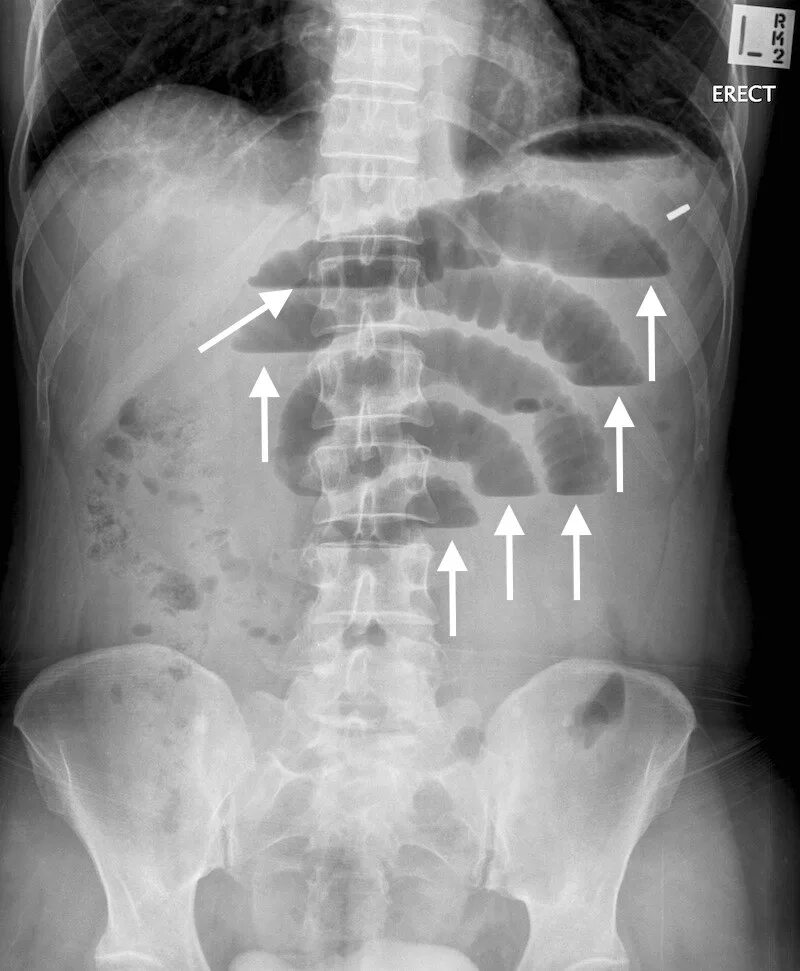

Симптом чаши